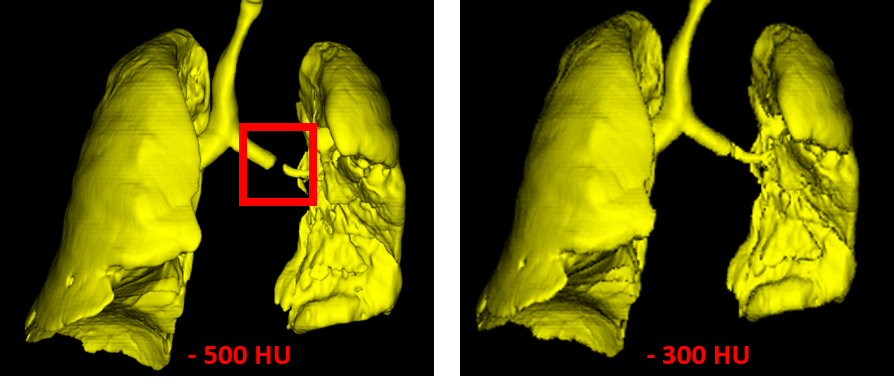

Стоит заметить, что важен правильный выбор порога рентгеновской плотности на начальном шаге порогового преобразования. Иначе в некоторых случаях может не оказаться связи между двумя лёгкими в результате низкого разрешения. Например, если считать, что воксели дыхательных органов имеют рентгеновскую плотность от -500 HU и менее, то в случае, приведённом ниже, выделение дыхательных органов как крупнейшего по объёму объекта приведёт к ошибке, так как отсутствует связь между двумя лёгкими. Поэтому следует повысить порог до -300 HU.